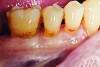

Fig 4 and Fig 5. Occlusal (Fig 4) and buccal (Fig 5) 42-month recall views of the Class I and Class V GIC restorations placed with bulk-fill EQUIA technique.